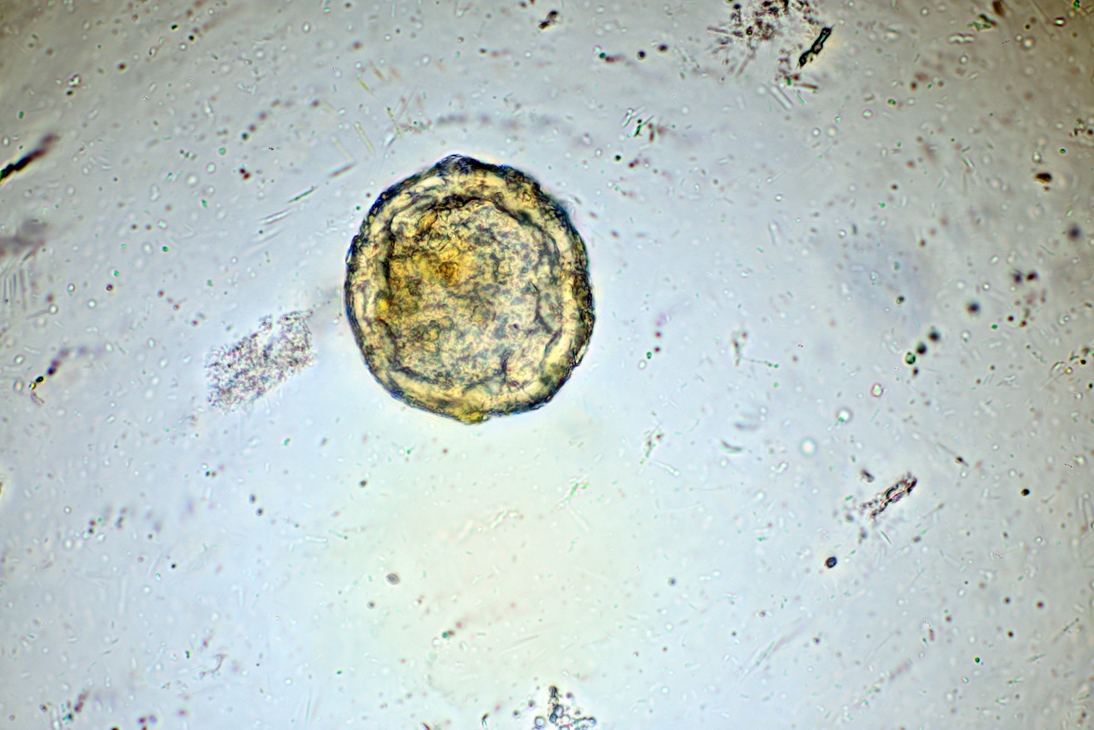

ich bin auf dem Gebiet vollkommener Anfänger, also gibt es für mich noch erhebliches Verbesserungspotenzial. Trotzdem traue ich mich mal. Vielleicht hat jemand eine Idee was die Objekte darstellen könnten? Aufgenommen ist das mit einem 40 Objektiv.

Im ersten Bild ist das Objekt in der Zentrifuge wohl mit einem Salzkristall aneinandergeraten.

ich möchte mich ein wenig mit der Parasitologie beschäftigen. Bei dem Präparat handelt es sich um eine Stuhlprobe aufbereitet nach einem kombinierten Sedimentations- und Flotationsverfahren. Daher ist das Kristall ein Salzkristall der Flotationslösung.

Zentrifugiert wurde mit 1500 U/min für 3 Minuten.

wow, so viel Backgroundinformationen sind da notwendig. Also der Durchmesser des "Ei's" (will ich mal so nennen) dürfte um die 60um betragen. Das Verfahren war ein kombiniertes Sedimentations und Flotationsverfahren. Flotationslösung mit NaCl. Das Tier ist ein Hund.